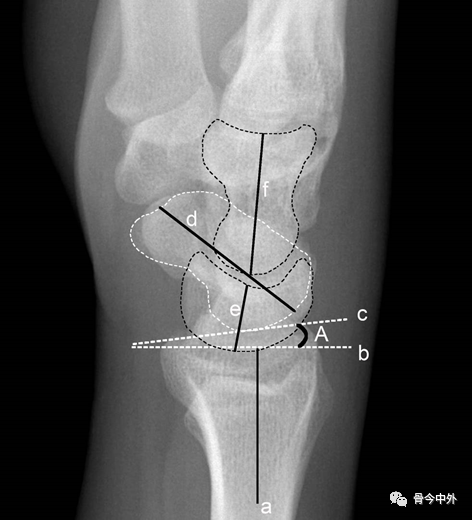

图4 a.桡骨纵轴线;b.桡骨纵轴线垂线;c.桡骨远端关节面切线;d.尺骨远端关节面水平线。A.桡骨内倾角;B.桡骨茎突长度;C.尺骨茎突长度 。

A.正常为15~35˚ 。若此角度改变,提示桡骨远端骨折或腕关节脱位。

B.正常为8~18mm,且桡骨茎突较尺骨茎突低1~1.5cm。若此长度改变,提示桡骨远端骨折。C.正常为2~8mm。若此长度改变,提示尺骨茎突骨折或尺骨茎突过长(尺骨茎突撞击综合症)

图7 a.舟骨、月骨切线;b. 月骨三角骨切线;c.尺骨远端关节面切线;d.腕骨总高度;e.头状骨长度。A.腕骨角;B.尺腕角 。

A.约130°。腕关节骨折、脱位时此角增大,此角减小见于Madelung畸形和卵巢发育不全。

B.正常为21~51˚。若此角度改变,提示腕骨骨折或腕关节脱位。

*腕骨高度指数:d与第3掌骨长度的比值,正常范围0.54±0.03。Nattrass腕骨高度指数为d/e,正常范围1.57±0.05。在月骨缺血坏死、不稳定型舟骨骨不连、腕关节不稳时,腕骨高度指数减小。